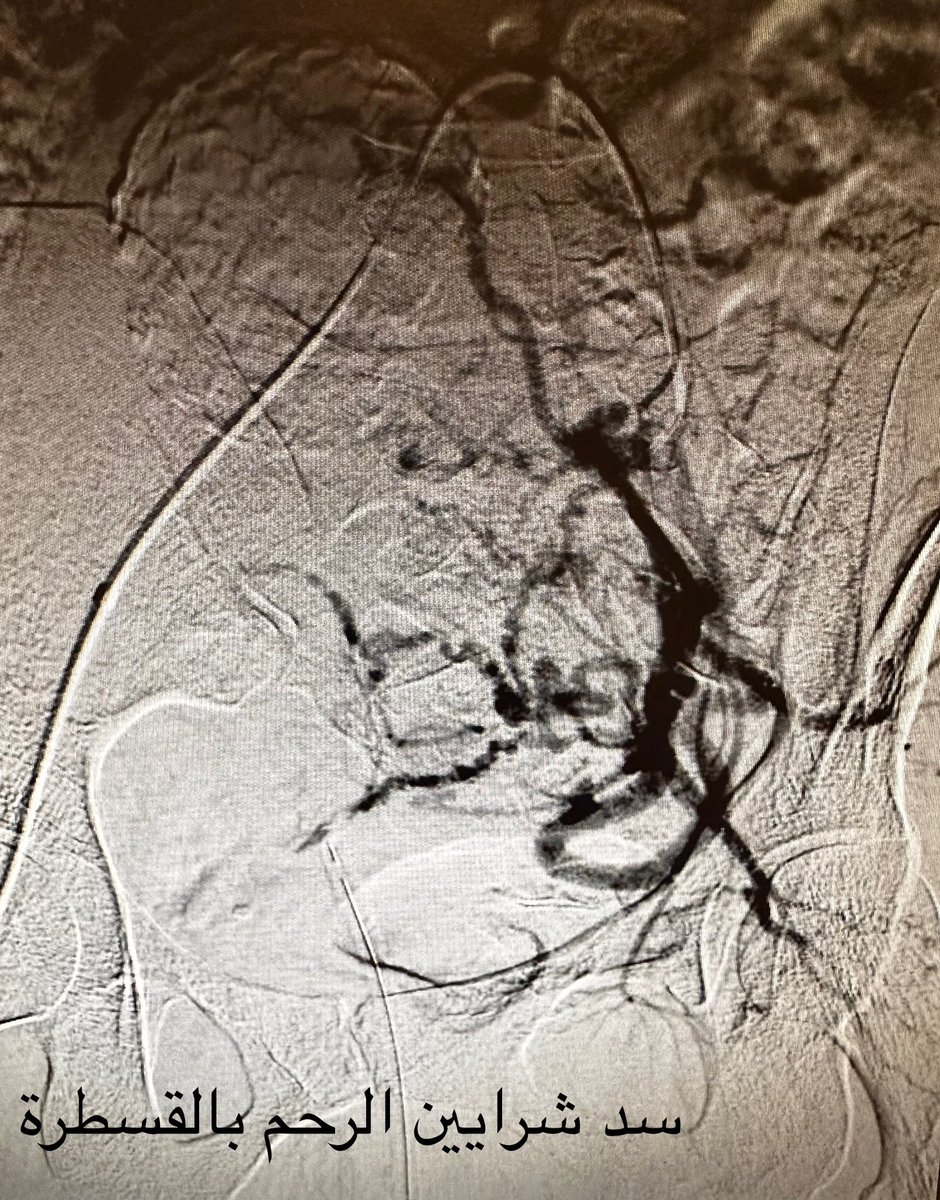

بعد 10 سنوات من العقم بسبب أورام الرحم الليفية، وبعد ان كادت تفقد رحمها في عمليات جراحية، خضعت مريضتنا للعلاج بالقسطرة. بعدها بسنتين، وضعت طفلة جميلة. قصة ملهمة بأن الطب الحديث والأمل يصنعان المعجزات! #الأشعة_التداخلية

بعد 10 سنوات من العقم بسبب أورام الرحم الليفية، وبعد   ان كادت تفقد رحمها في عمليات جراحية، خضعت مريضتنا للعلاج بالقسطرة. بعدها بسنتين، وضعت طفلة جميلة.

قصة ملهمة بأن الطب الحديث والأمل يصنعان المعجزات!

#الأشعة_التداخلية